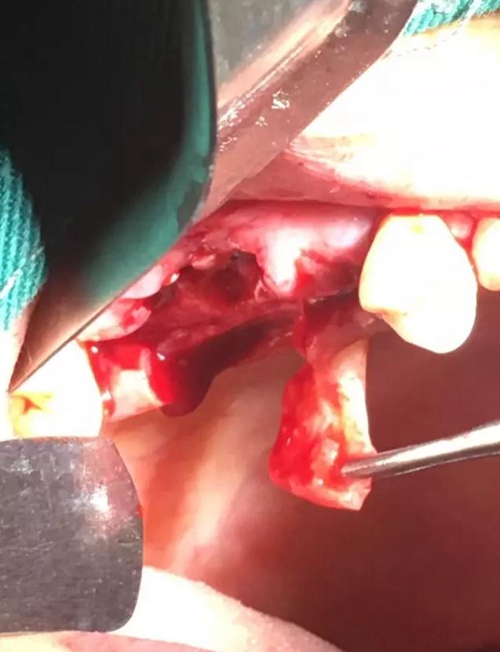

【病例分享】內(nèi)提,用自體骨柱,不用骨粉

4.jpg